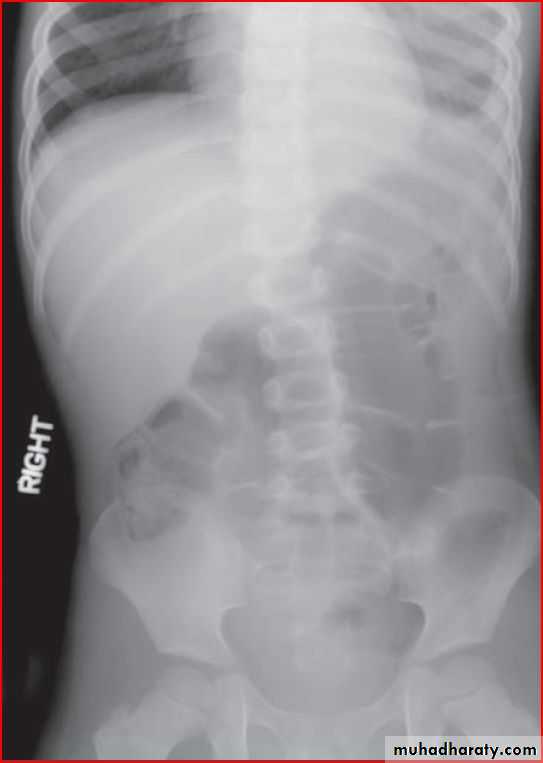

X ray of wrist showing cupping fraying splaying

Dx >>> rickettwo labrotary investigation 1. alkaline phosphatase elevation

2. s.calicium low or normal

ricket